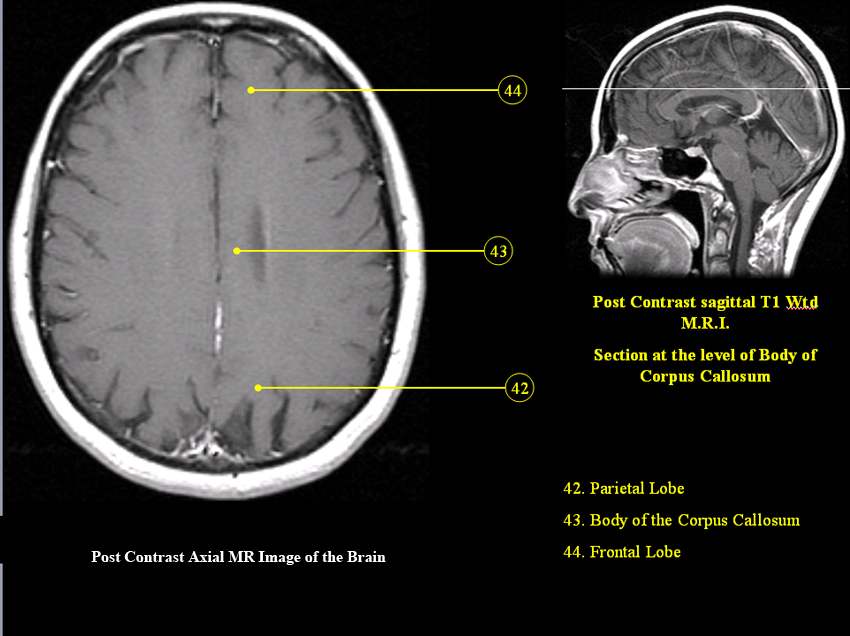

MR Brain and Spine